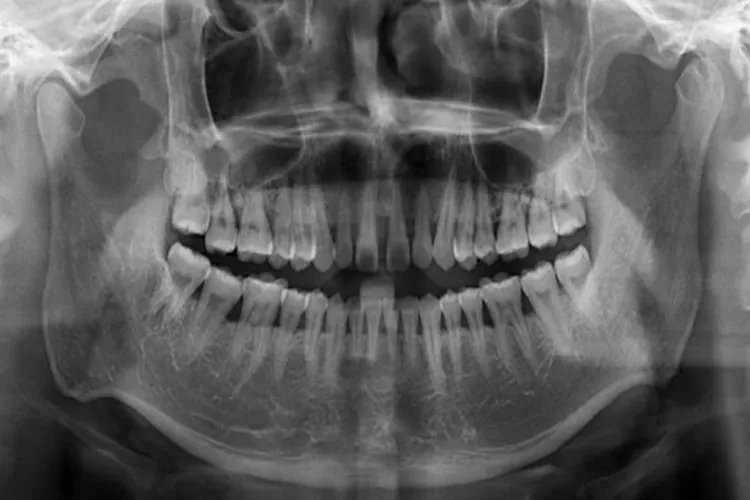

的有关信息介绍如下:概述牙槽骨是上下颌骨包围和支持牙根的部分,由牙根支撑呈凹槽状。骨质较疏松,且富于弹性,是支持牙的重要组织。形态牙槽骨是上下颌骨包围和支持牙根的部分,又称牙槽突,呈凹槽状。牙槽骨由固有牙槽骨和支持骨组成,X线片上,固有牙槽骨显示为环绕牙根的白色阻射线。容纳牙根的窝称牙槽窝,在冠方的牙槽窝的游离端称牙槽嵴。牙槽嵴的形态在前牙区为圆柱状,磨牙区为扁平状,而在颊舌侧变薄甚至消失。

生物特征牙槽骨是高度可塑性组织,也是全身骨骼中变化最活跃的部分,它的变化与牙的发育和萌出、乳牙替换、恒牙移动和咀嚼功能等均有关系。生理状态下,牙因(牙合)面及邻接面的磨耗而不断发生生理性的移位,牙槽骨也随之产生吸收和增生的改建。在牙萌出和移动的过程中,受压力侧的牙槽骨骨质发生吸收,而牵张侧的牙槽骨骨质增生。临床上进行错(牙合)畸形矫治的生物学基础也是利用牙槽骨的高度可塑性,利用一定的力学刺激促进牙的移动。